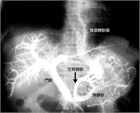

1. 食道・胃静脈瘤は慢性肝疾患などによる門脈圧亢進症に伴って代償的に形成される側副血行路の1つである。

1. 胃静脈瘤:内視鏡的塞栓術(Histoacrylによる)、バルーン閉塞下逆行性経静脈的塞栓術(balloon-occluded retrograde transvenous obliteration:B-RTO)を行う。